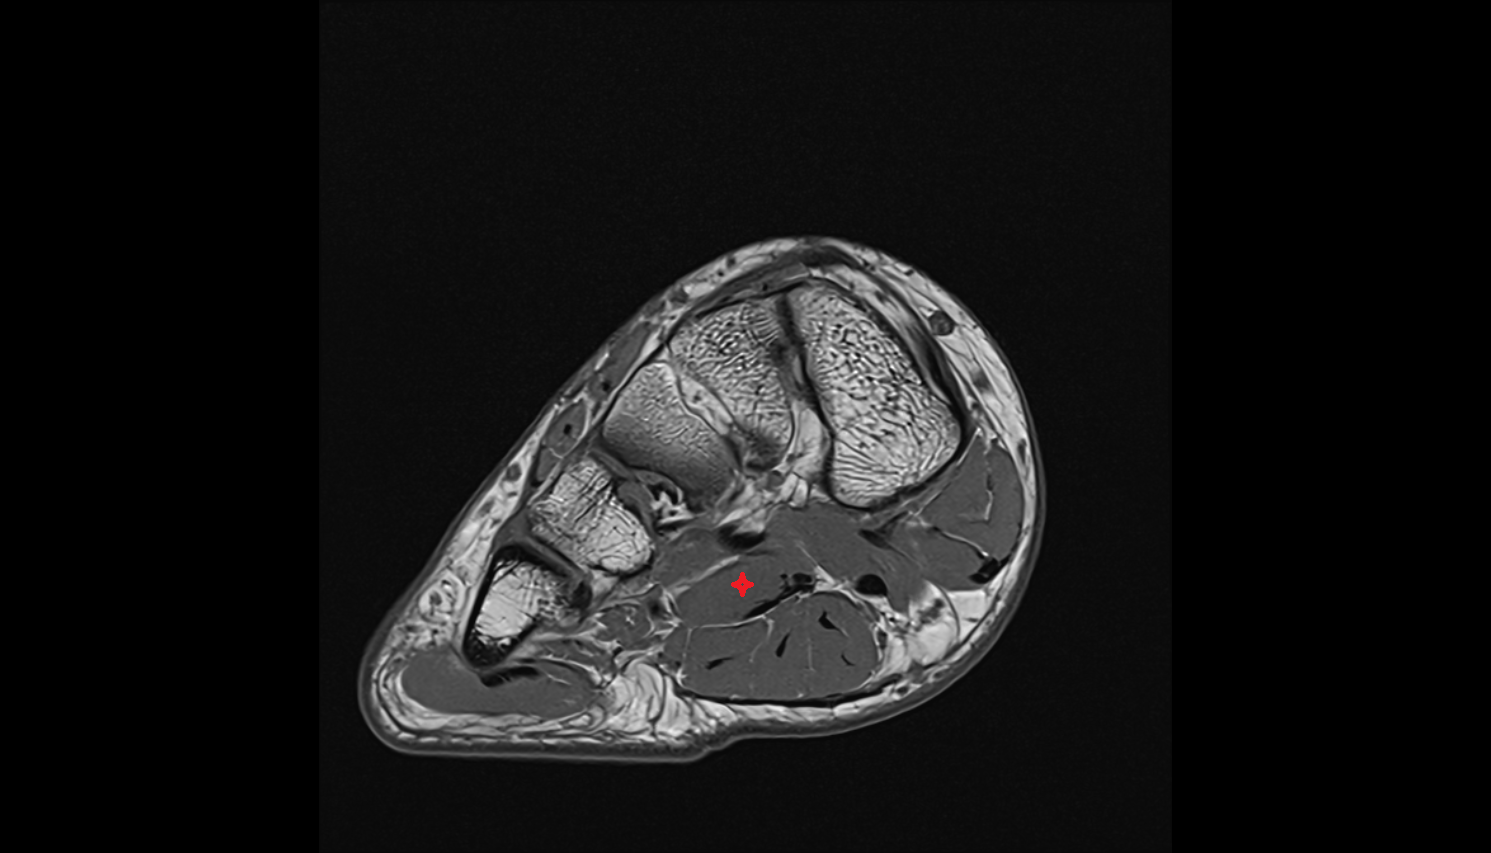

- Tibialis posterior muscle

- Flexor digitorum longus muscle

- Flexor hallucis longus muscle

- Quadratus plantae muscle

- Abductor hallucis muscle

- Flexor digitorum brevis muscle

- Abductor digiti minimi muscle

- Tibialis posterior tendon

- Flexor digitorum longus tendon

- Flexor hallucis longus tendon

- Flexor retinaculum

- Posterior tibial artery